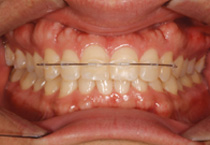

Anterior Crossbite

Case 1

Smile Line case 1 2022.06.14

2022.06.14

Smile Line case 1 2022.10.06

2022.10.06

Smile Line case 1 2023.02.07

2023.02.07